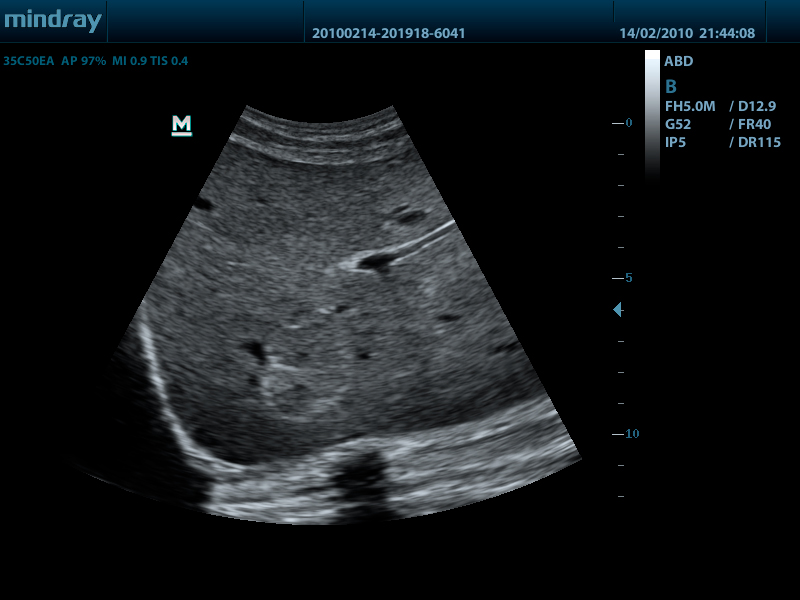

Конвексный датчик 35C50EA (2.0/3.5/4.5/5.0/Н5.0/Н6.0) R50

Внутриполостной датчик 65EC10EA (5.0/6.5/7.5/8.5/Н8.0/Н9.0 МГц, R-10 )